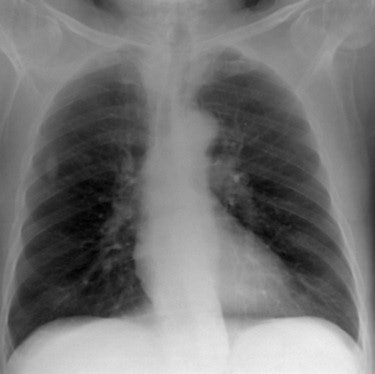

The researchers found statistically significant correlations between the visual scores that represented clinical image quality and the CNR representing physical image quality. For CNR, R = 0.87 (p < 0.033), while for eDE, R = 0.77 (p < 0.008).

As well as the link between clinical and physical image quality, the results of this paper also demonstrate that chest CR can be carried out with tube voltages much lower than those used traditionally, given that both clinical and physical image quality improve as tube voltage is decreased, he added.